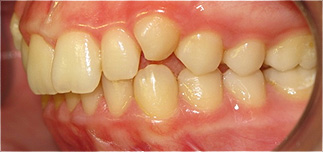

Apinhamento dentário com os dentes caninos em desoclusão (classe II, divisão 2).

![]() |

Após dois anos de tratamento ortodôntico.